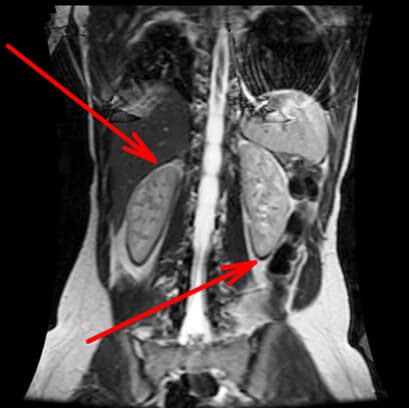

Description:

The next artifact is the chemical shift. This artifact is visible at the level of a water/fat interface in order to code the frequency. One side of the liquid object in a fatty environment shows that its outline is enhanced by a hyper signal border. However, the opposite is enhanced by a hypo signal border. This can also appear for a fatty object in a liquid environment. This artifact is for coding the frequency: it is called the chemical shift.

On this image, look at the areas where the red arrows point, and you will see the effect of chemical shifts around the kidneys.

A strip of hypo and hyper signals on each side of the water / fat interface in order to code the frequency.

Origins:

We have seen that the protons that are exposed to a magnetic field rotate with a specific frequency which is Larmor frequency. In fact, the molecular environment of Hydrogen protons will slightly impact their precession frequency. This difference in rotation speed will be the source of this chemical shift artifact.

The difference in the rotation speed of the Hydrogen protons of water and fat is always 3.4 ppm. This means that for a magnetic field of 1.5 T, the difference is 208 Hz. We have seen that the signal was moved by Fourier Transformation by its frequency. Because of this difference in the rotational speed of the water protons relative to those of fat, they will be artificially shifted against each other.

If this 208 Hz are shown in more pixels, then these signals will be located in the wrong position. Notice that around the organ, there will be a part where the signals of water and fat will add up (H2O + fat = white stripe), a part where there is no organ (H2O = normal signal the organ), and a part with no signal (nothing = black band). This is the chemical shift.